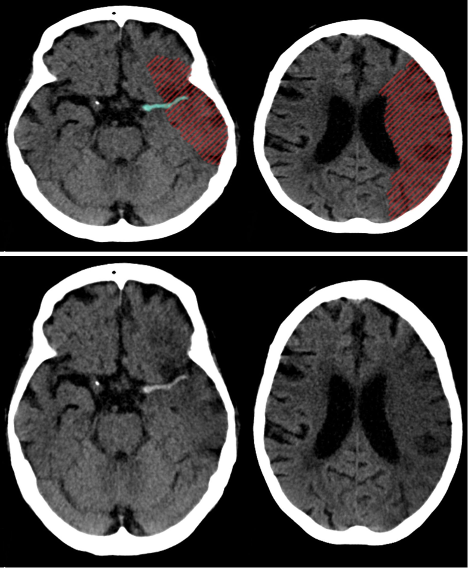

D) Special types of infarction; Lacunar infarction

Infarction that are less/smaller than 1cm

Chronic lacunar infarcts

CT head (without contrast; axial plane)

Multiple, very small, sharply-demarcated hypodense lesions are present in the basal ganglia, left internal capsule , and right thalamus . Additionally, there is diffuse cerebral atrophy with prominence of the sulci and ventricles.